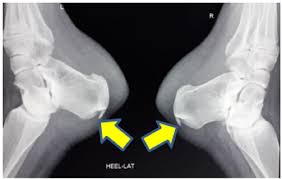

Haglund's syndrome is a group of signs and symptoms consisting of haglund's deformity (which is an exostosis of the posterior calcaneal tuberosity) in combination with retrocalcaneal bursitis. See more ideas about radiology, radiography, radiology imaging. (review and first experience surgical treatment. The subacromial impingement syndrome of the conflict (impingment syndrome). Insertional achilles tendinitis and haglund's deformity. Insertional achilles tendinopathy retrocalcaneal bursitis haglund deformity. It is often accompanied by achilles tendinitis. Adrenocortical carcinoma associated with adrenogenital syndrome in a child. Insertional achilles tendinopathy retrocalcaneal bursitis haglund deformity (i.e. Varan a, unal s, ruacan s, vidinlisan s. Radiographic evaluation of haglund's deformity. Haglund syndrome refers to the triad (haglund triad) of: A full range of orthopedic services, from diagnosis to full recovery.

1 department of radiology and inje university busan paik hospital, inje university college of haglund syndrome was first described in 1928 as retrocalcaneal bursitis associated with an. Oral radiology, principles and interpretation. Haglund's syndrome a bump on the back of your heel that can become inflamed. Department of radiology and imaging, hospital for special surgery, weill medical college of cornell university, 535 east 70th street, new. Haglund syndrome refers to the triad (haglund triad) of: